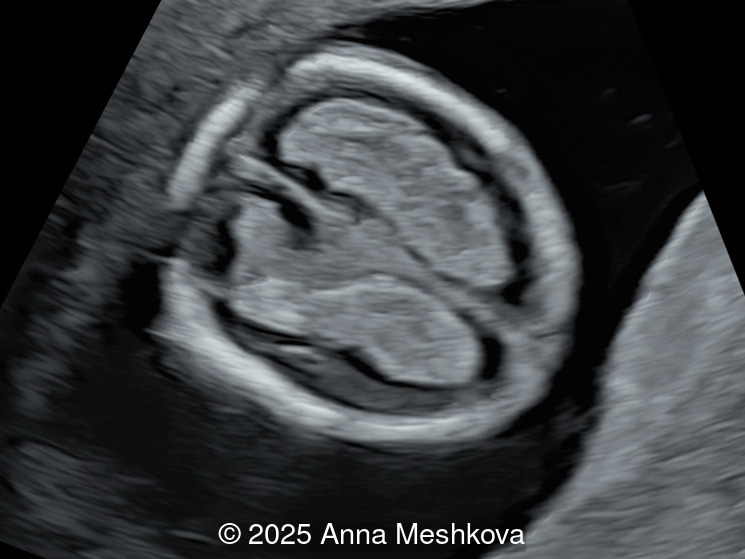

Image 1

• Image 1:  Transverse section of the brain at the level of choroids. Subtle supporting sign of relatively large choroid plexuses and low surrounding cerebrospinal fluid known as the "dry brain" sign.

4.  Dry Brain Sign is characterized by an exaggerated size of the choroid plexuses filling the lateral ventricles due to diminished cerebrospinal fluid in the ventricular system.  Unidirectional leakage of fluid towards the open spinal defect results from a pressure gradient between the “high-pressure” CSF-filled choroid ventricles and, “low-pressure” spinal cord, which produces posterior and caudal displacement of the mesencephalon. As a result, the reduced fluid in the lateral ventricles causes the choroid plexuses to fill the cranial cavity [4-5].

Dry brain sign is demonstrated in the axial view of the fetal head at 13 weeks gestation. Note the large and long choroid plexus in comparison to head size in a fetus with open spina bifida.

Image 10 Dry brain sign is demonstrated in the axial view of the fetal head at 13 weeks gestation. Note the large and long choroid plexus in comparison to head size in a fetus with open spina bifida.